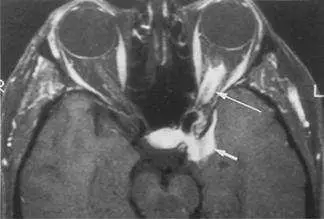

40 歲女性患者,主訴幾個月來左眼視力逐漸減退,接受磁振造影檢查,圖為注射顯影劑後並且經過抑制脂肪處理的 T1 加權影像,圖中箭號所指最可能的病變是:

本題考核眼窩磁振造影(MRI)的影像判讀,重點在識別視神經鞘腦膜瘤(optic nerve sheath meningioma, ONSM)的特徵性影像表現,並與其他視神經病變(視神經膠質瘤、視神經炎、眼窩假性腫瘤)做鑑別診斷。本例為40歲女性,數月來漸進性單側視力減退,MRI 為注射顯影劑後加脂肪抑制的 T1 加權影像,是 ONSM 最佳診斷序列。

本題提供的為軸位(axial)後顯影劑注射、脂肪抑制 T1 加權 MRI 影像。兩側眼球清晰可見,球後區域可觀察到:

- 左側視神經(箭號所指):視神經鞘呈明顯強化(高訊號),包繞視神經形成典型的「軌道狀強化(tram-track sign)」——即視神經本身訊號偏低(不強化),而其外圍的腦膜鞘呈周圍環形強化。

- 強化型態:腫塊沿視神經呈管狀/筒狀擴展,強化均勻且顯著,是 ONSM 的典型特徵。

- 脂肪抑制序列的意義:眼窩脂肪訊號已被抑制(低訊號),使強化的腫瘤更加突出,清楚顯示強化範圍沿神經鞘分布。

- 視神經本身:於強化的鞘中可隱約辨別中央低訊號的視神經,此「神經中央條紋」伴周邊環形強化,軸位即呈 tram-track sign,冠狀位則呈 doughnut sign(甜甜圈徵象)。

此影像表現高度符合視神經鞘腦膜瘤(optic nerve shea